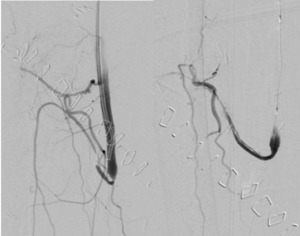

On day 11 Doppler signals were again lost, with visible hypo-perfusion. Angiography was repeated with an identical approach, demonstrating a patent anastomosis with thrombosis at the same site artery. Catheter-directed thrombolysis was repeated using 100,000 units of urokinase. Angioplasty with balloon dilatation was performed, though stent placement was not possible due to the tortuosity of the vessel. There was improvement in angiographic flow (Figure 2) and the flap regained good colour and capillary refill with the return of an arterial Doppler signal.